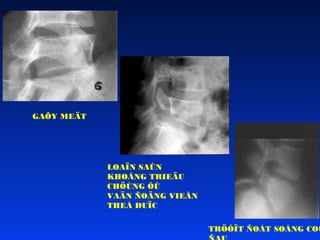

DÒCH TEÃ HOÏCDÒ TAÄT HUÛY EO ÑOÁT SOÁNG  XUAÁT ÑOÄ TRONG DAÂN SOÁ:2-4%  XUAÁT ÑOÄ Ôû NGÖÔØI CHÔI THEÅ THAO: 525%  YEÁU TOÁ THUAÄN LÔÏI VEÀ CHUÛNG TOÄC VAØ DI TRUYEÀN  TUOÅI XUAÁT HIEÄN: 5 – 8 TUOÅI = LOAÏN SAÛN  GAÕY MEÄT ÔÛ TUOÅI DAÄY THÌ  TUØY THUOÄC VAØO MOÂN THEÅ THAO VAØ TRÌNH ÑOÄ CHÔI THEÅ THAO

GAÕY MEÄT LOAÏN SAÛN KHOÂNGTRIEÄU CHÖÙNG ÔÛ VAÄN ÑOÄNG VIEÂN THEÅ DUÏC TRÖÔÏT ÑOÁT SOÁNG COÙ

GAÕY DO STRESS CAÙCYEÁU TOÁ THUAÄN LÔÏI • Loaïn saûn coù saün • Daây chaèng loûng leûo quaù möùc • Moûm khôùp döôùi ñoát TL 4 quaù daøi • Daùng ngöôøi nghieâng ra tröôùc nhieàu